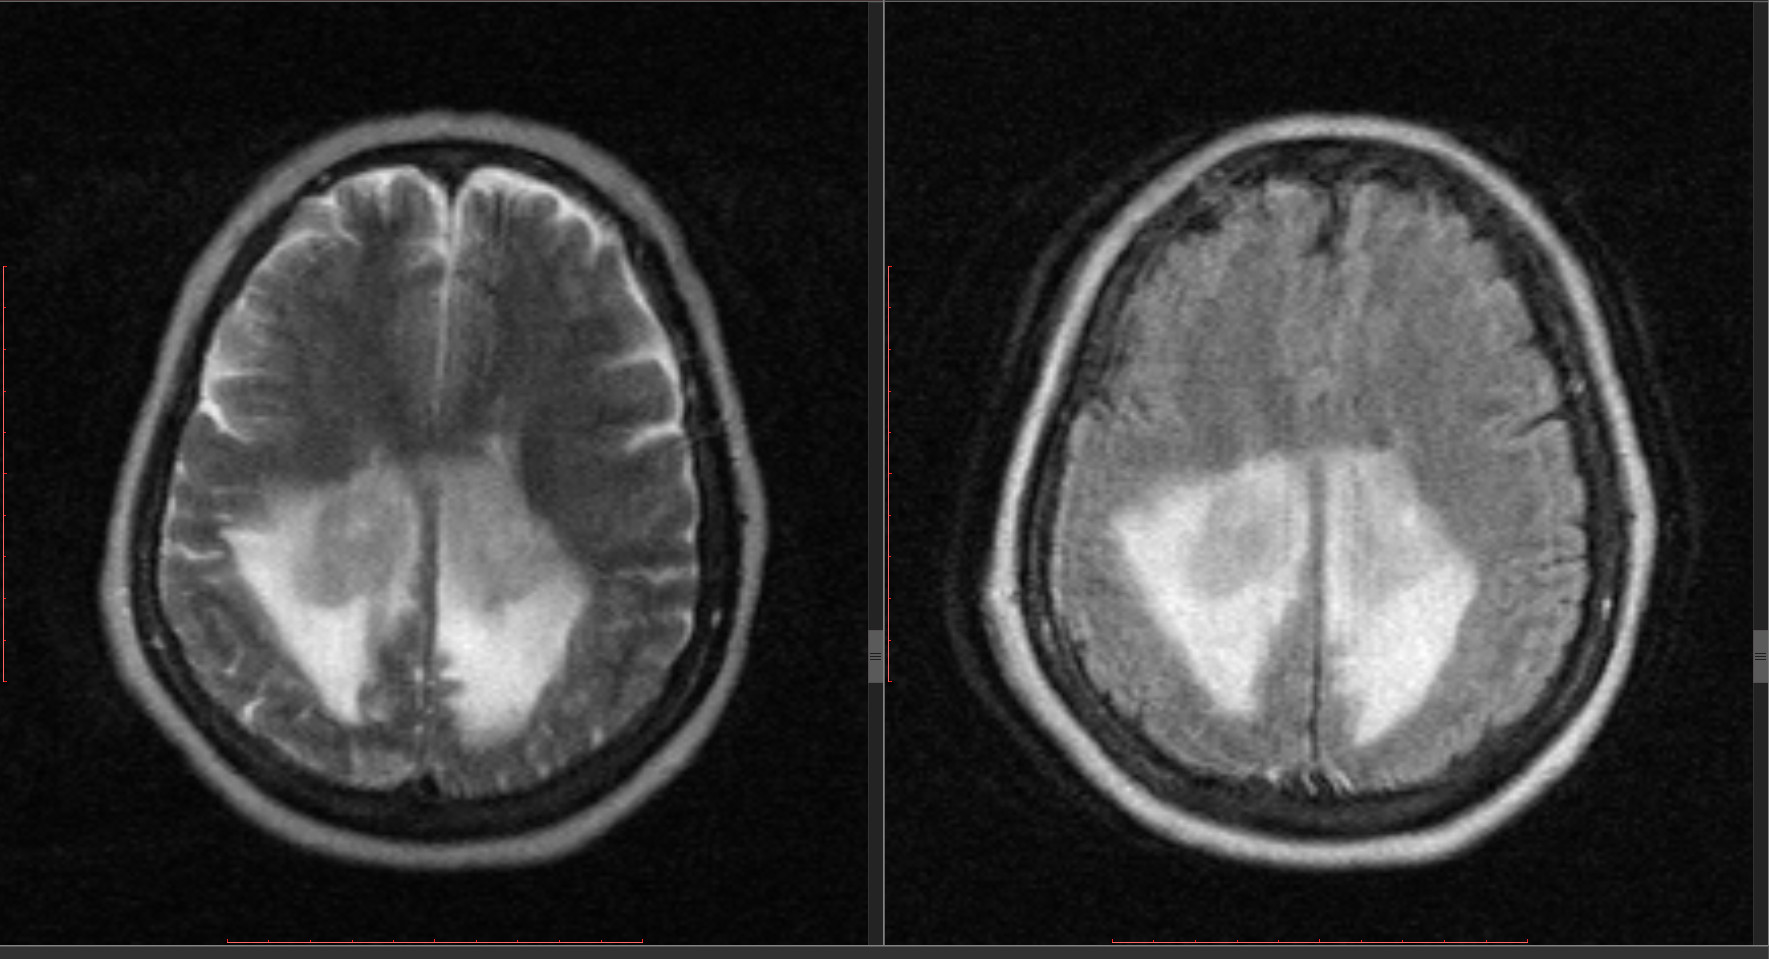

Я бы на 1-е место поставил первичную лимфому ЦНС (надо СПИД исключить). В дифряде - глиобластома, лимфома. Теоретически еще центральная нейроцитома поражает мозолистое тело, но кажется это не тот случай.

глиоматоз с вазогенным отеком не тянет,да и лимфома тоже редкость high-grade глиома это(cbf map)

Не глиоматоз и не нейроцитома уж точно.

Надо делать перфузию и диффузию и уже после этого делать выводы что это. Как без контрастирования и всего прочего можно судить об образовании? Если только на интуиции, но это не аргумент.

CBV и скорректированный CBV, K2 очень координально отличаются у лимфомы и глиобластомы, различить можно без труда, а наши фантазии - что же это на стандартной неусилинной МРТ, думаю, мало кому интересны :)

Спасибо за хорошую книжку

Правильно ли я понял Вашу мысль, что здесь более вероятны лимфома либо ГБ? И автору в принципе, использовав DTWI, можно более менее определиться: лимфома (сама строма опухоли) поярче будет? Хотя конечно, я понимаю, что аппаратные ограничения не раполагают к определенности в формулировках...